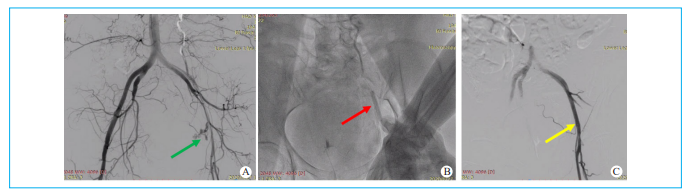

①腹膜后出血:术中密切观察患者血压,同时需要注意观察透视下膀胱形态,若出现受压、不对称或挤压向一侧等征象应怀疑存在腹膜后出血。②胸腹主动脉夹层:术毕造影可明确是否存在夹层,是否影响肾动脉、肠系膜上动脉和腹腔干等重要内脏动脉,密切观察患者肾功能、尿量、腹痛和排便及排气情况(图5D)。③髂股动脉破裂:若回撤大鞘髂时动脉造影或者腹主动脉造影显示入路穿孔或破裂渗血(图7A),应当立即干预动脉破口。④下肢动脉闭塞:ProGlide或者8F Angioseal封堵后可能导致下肢动脉闭塞,术毕足背动脉及内踝动脉不能扪及,下肢皮温低,严重时患者常感觉下肢疼痛。

动脉长鞘怎么置入【文章精选】经导管主动脉瓣置换术下肢入路评估处理策略与技巧_https://www.jmylbn.com_新闻资讯_第7张

图7 副入路破裂渗血球囊压迫止血  A. 腹主动脉造影显示左侧股总动脉渗血(绿色箭头);B. 球囊序贯压迫左侧股总动脉(红色箭头);C. 造影显示左侧股总动脉通畅且无渗血(黄色箭头)。

①球囊序贯压迫技术:通过对侧副入路,经翻山路径送导丝至主入路的股浅动脉,采用5~6mm的外周球囊行动脉破口处压迫,同时给予鱼精蛋白中和肝素,每次压迫3~5min,然后松开再次造影明确破口渗血情况,重复采用球囊间断压迫,直至破口处完全停止渗血[9],同时避免下肢长时间缺血,一般适用于导丝穿孔,破口比较小的动脉渗血抢救(图7)。②覆膜支架抢救性植入:腹主动脉夹层以及髂股动脉破口比较大且渗血量大,则可考虑直接植入直径8~10mm的覆膜支架,根据造影情况决定是否行后球囊扩张(图5E)。③外科切开修复:当补充ProGlide或8F Angioseal处理后仍有较多渗血,则需要外科切开缝合穿刺点和血管破口(图8)。